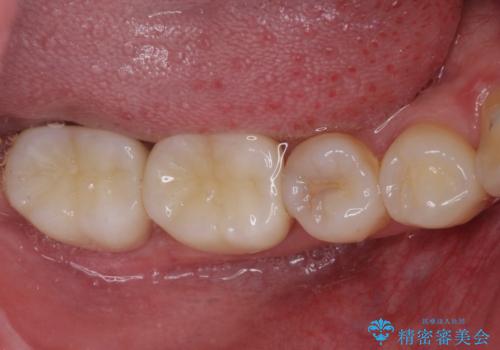

- 右下奥歯の虫歯がしみて痛いとのことで来院された患者様です。

神経近くにまで及ぶ大きな虫歯でしたが、速やかに処置を行い、痛みは即日解消されました。

虫歯が大きかったため、クラウンによる補綴治療が必要になる旨をお伝えしたところ、矯正治療にも興味があるとのことでした。

短期間で手間のかからない方法がご希望でしたので、ワイヤー装置による矯正治療を行うこととし、矯正治療後に右奥2歯をセラミッククラウンにて補綴することとしました。